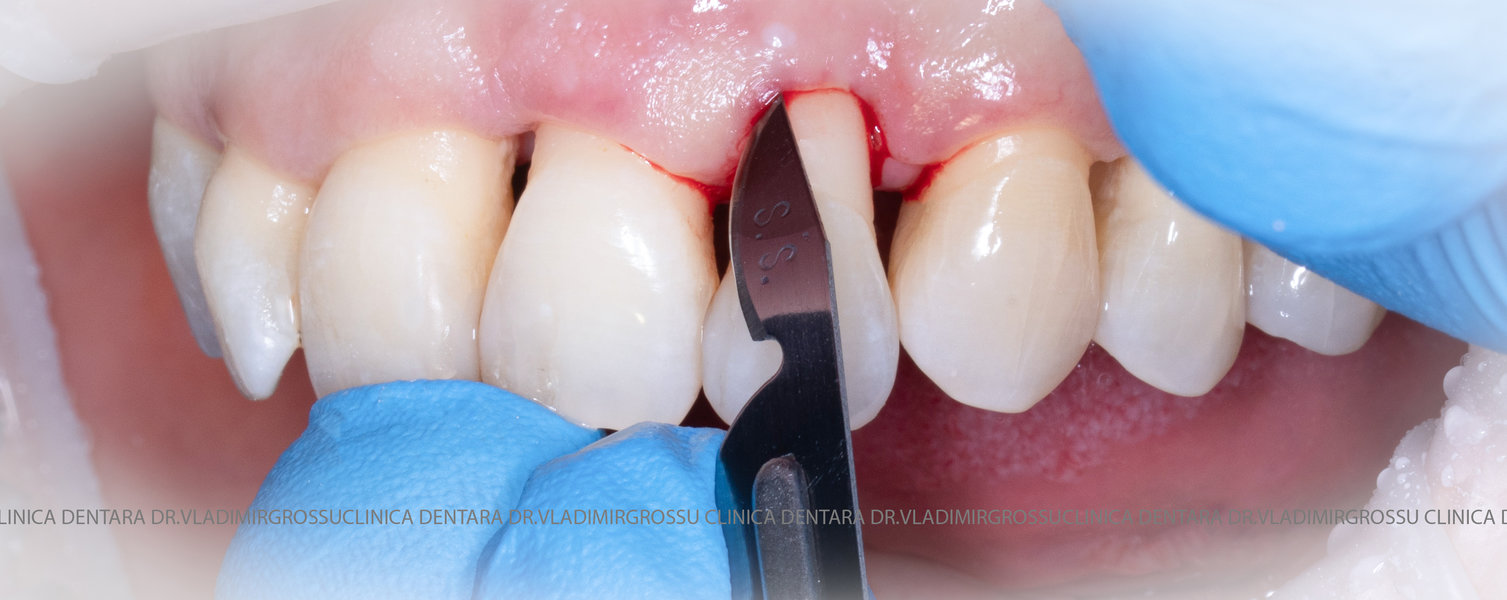

Aditia gingivală este o procedură chirurgicală ce corectează diverse probleme estetice și funcționale, cum ar fi recesiunea gingivală. În implantologia modernă, aditia de țesut moale este utilizată aproape în fiecare intervenție de inserție a implantului dentar pentru a asigura un aspect estetic natural și o bună integrare a implantului în cavitatea bucală.

Adiția osoasă are un rol crucial pentru poziționarea corectă și stabilă a implanturilor dentare. Clinica stomatologică Dr. Grossu din Chișinău promovează o abordare chirurgicală estetică și predictibilă, adaptată fiecărui caz în parte.

Medicii noștri au o vastă experiență atât în chirurgia estetică, cât și în protezarea cu un grad înalt de naturalitate, ceea ce ne permite să gestionăm cu succes și cele mai complexe cazuri.